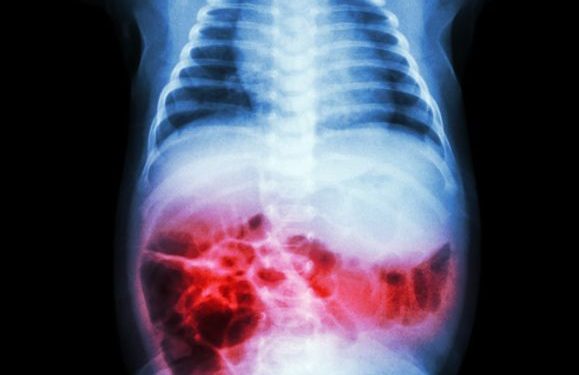

Diagnosis is based on the appearance of the skin and on tests for the presence of gas bubbles under the skin. The doctor also needs to look at the area of infection on X-rays.